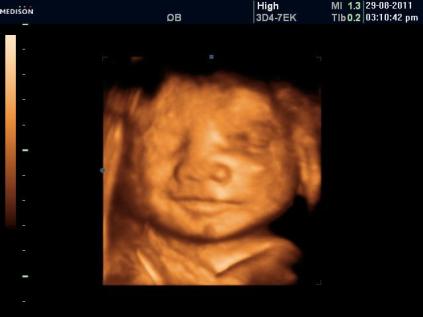

4D scan of Jah…:D

I know it looks abit scary…

But really fun to see his expression and imagine what he might look like..